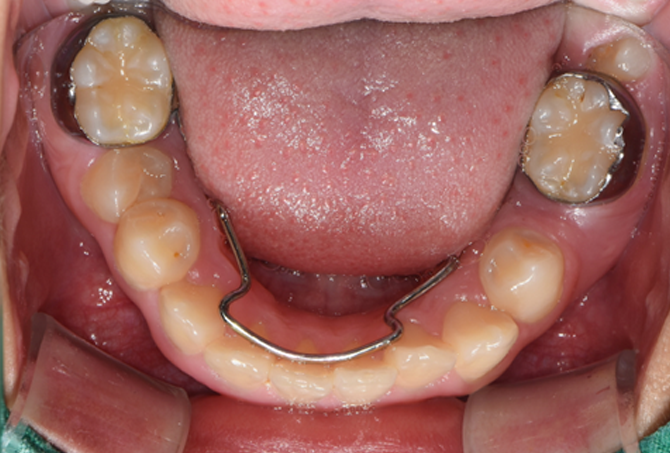

• STEP 04 치료 완료 후 유지 관리

치료 종료 후 유지장치를 착용하며

치아 위치를 유지합니다.

• STEP 01 1단계 (1차 교정)

만 6~9세경, 영구치 맹출 유도 및 턱뼈 성장 부조화 개선을 위한

성장 조절 치료를 진행합니다.

(페이스마스크, 헤드기어, 확장 장치 등)

• STEP 02 2단계 (2차 교정)

만 12세~13세, 영구치가 모두 맹출한 후, 필요에 따라

치아 하나하나의 배열을 정교하게 다듬는 교정을 진행합니다.

(브라켓 교정, 투명교정 등)